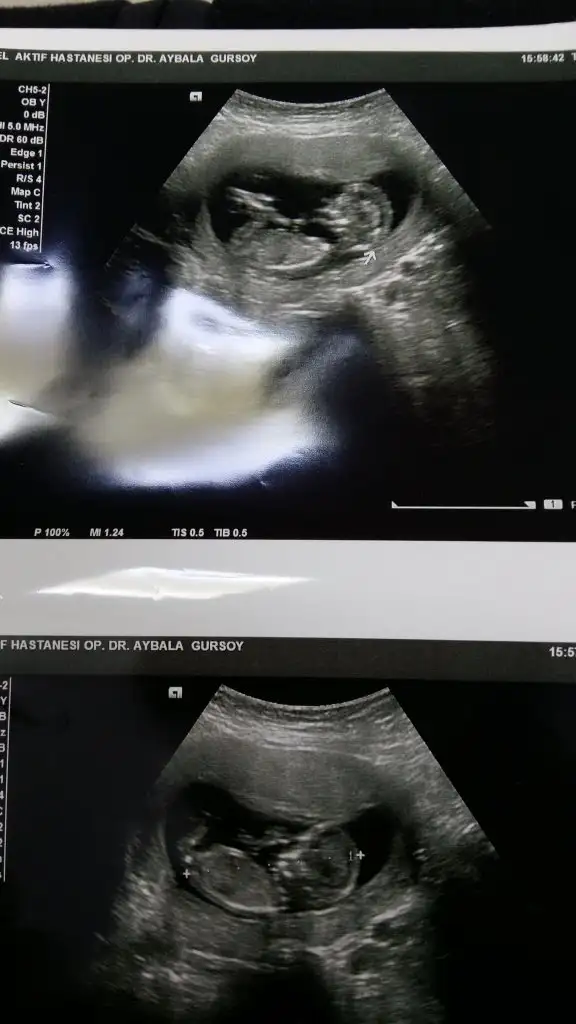

Arkadaşlar benimki kızmı erkekmi bilemedim.yardım edin.

Eklentiler

• 20181229_153001.webp

47,4 KB · Görüntüleme: 188

• Screenshot_20181229-162636_Gallery.webp

14,1 KB · Görüntüleme: 226